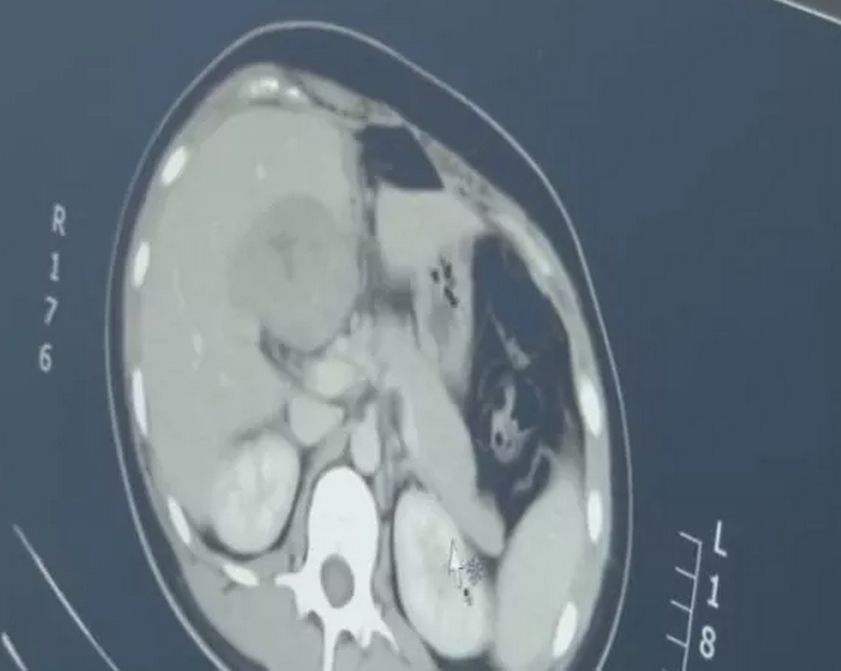

于是给尤女士做了CT

最后竟然在肝脏部位

找到了胚胎……

这是一个罕见的宫外孕病例

据介绍,宫外孕常见于输卵管附近,胚胎跑到肝脏部位极为罕见,很容易引发大出血,危及生命。